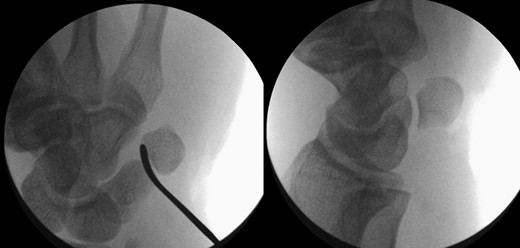

The patient was taken to theatre the following day where a closed reduction of the dislocated pisiform was attempted, however it was unsuccessful. Therefore we then proceed to an open reduction. This was performed through a volar approach through the flexor carpi ulnaris tendon where the piso-hamate joint was exposed and a capsular release performed. This allowed the pisiform to reduce back in to the anatomical position Fig 3. The wrist was immobilized in a neutral position. The patient was followed up in the clinic in two weeks, six weeks, three and six months. The check X-ray performed at the end of six months demonstrated the pisiform remain well reduced, Fig 4. He subsequently regained full a range of motion within the wrist and was further discharged from the clinic.

Image intensifier pictures showing reduction of dislocated pisiform bone.